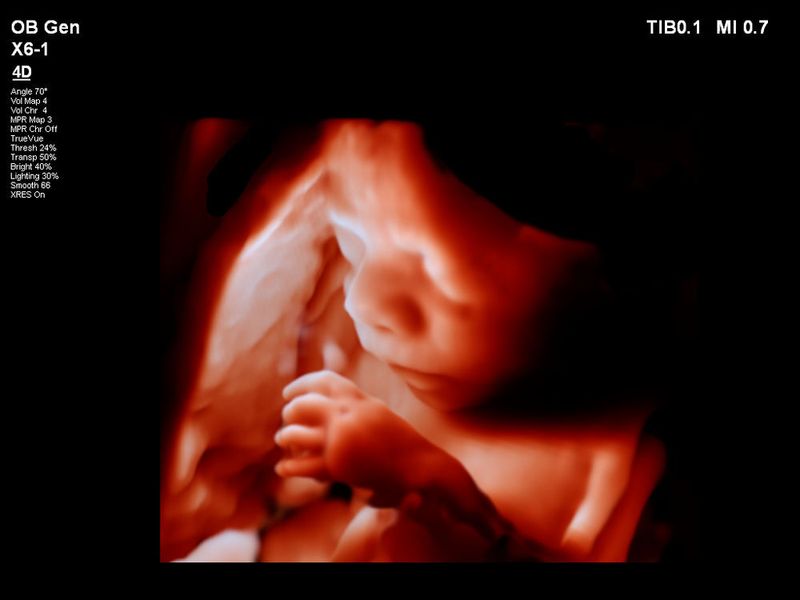

Medizinische Bildgebung gestern, heute und morgen